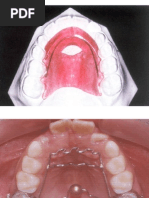

. A la sexta semana se forma la lmina dental que origina los dientes. En

el recin nacido los maxilares estn reducidos a su simple porcin

basilar, mientras que las ramas horizontales se encuentran disminuidas.